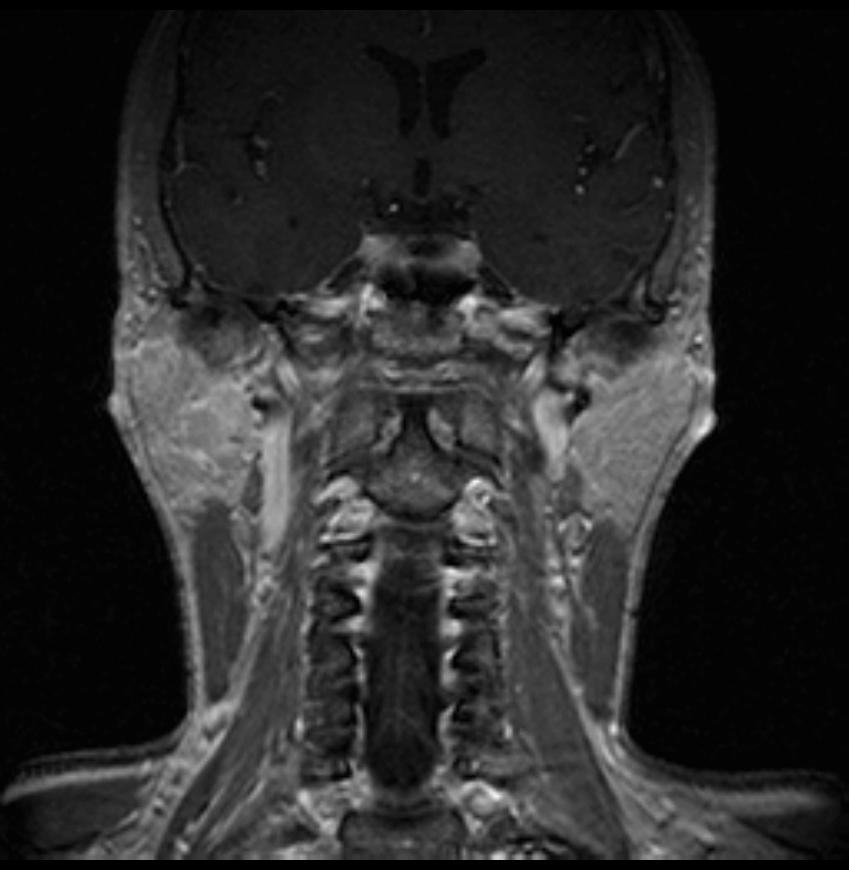

06.06.2011 МРТ - головы и шеи.

Пацентка 36 лет, с жалобами на припухлось в околоушной области справа.

В глубокой доле  правой околоушной железы  на фоне неизмененной паренхимы зона  гетерогенного по Т2, гипоинтенсивного по Т1  с единичными гиперинтенсивными включениями.При контрастировании- накопление контраста диффузное неоднородное и по периферии.Рискну предположить злокачественное образование ( аденокарцинома) с низкой степенью злокачественности( есть капсула, экспансивный рост).Сильно не расстреливайте.

Проблема в том, что перед челюстно-лицевым хирургом стоит распространенность любого объемного процесса, в данном случае все упирается в возмможную травму лицевого нерва и конечно же с дальнейшим его парезом, а ведь женщина  еще молодая. Образование имеет тонкостенную оболочку, по структуре неоднородно, с наличием кальцината, при этом МР-сигнал от окружающих анатомических структур(как костных так и мышечных) не изменен, т.е. об инфильтративном росте речи не идет, в какой то степени доброкачественное. В конкретном случае лицевой нерв с ретромандибулярной веной просто несколько оттеснен.

По гистологии аденома околоушной слюнной железы, но после удаления пока сохраняется парез лицевой мускулатуры, возможно временный.